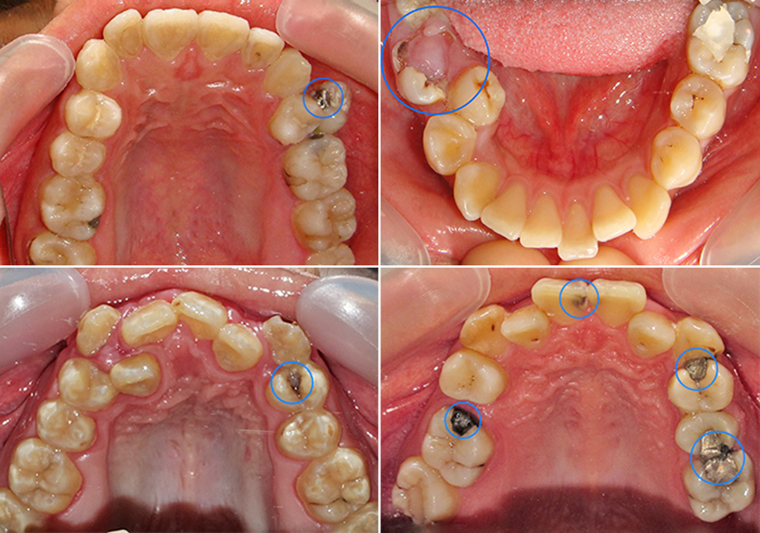

齒列不整的牙齒經常存有食物堆積的死角,而存有食物堆積的死角的牙齒則易造成清潔不易,牙齒清潔不易會促使牙齒產生牙結石與牙周病 (圖4)。

(圖4)齒列不整的牙齒經常存有食物堆積的死角,而存有食物堆積的死角的牙齒則易造成清潔不易,牙齒清潔不易會促使牙齒產生牙結石與牙周病。

牙周病發生初期缺乏臨床症狀,當發現牙周病存在時,牙周病經常已進入嚴重狀況,齒根周邊骨骼嚴重缺失,無法支持與固定牙齒。 而最終造成牙齒鬆動或不正常移動 (圖5)。

(圖5)牙周病發生初期缺乏臨床症狀,當發現牙周病存在時,牙周病經常已進入嚴重狀況,齒根周邊骨骼嚴重缺失,無法支持與固定牙齒。藍線代表健康齒槽骨高度,紅線代表齒槽骨萎縮後高度。